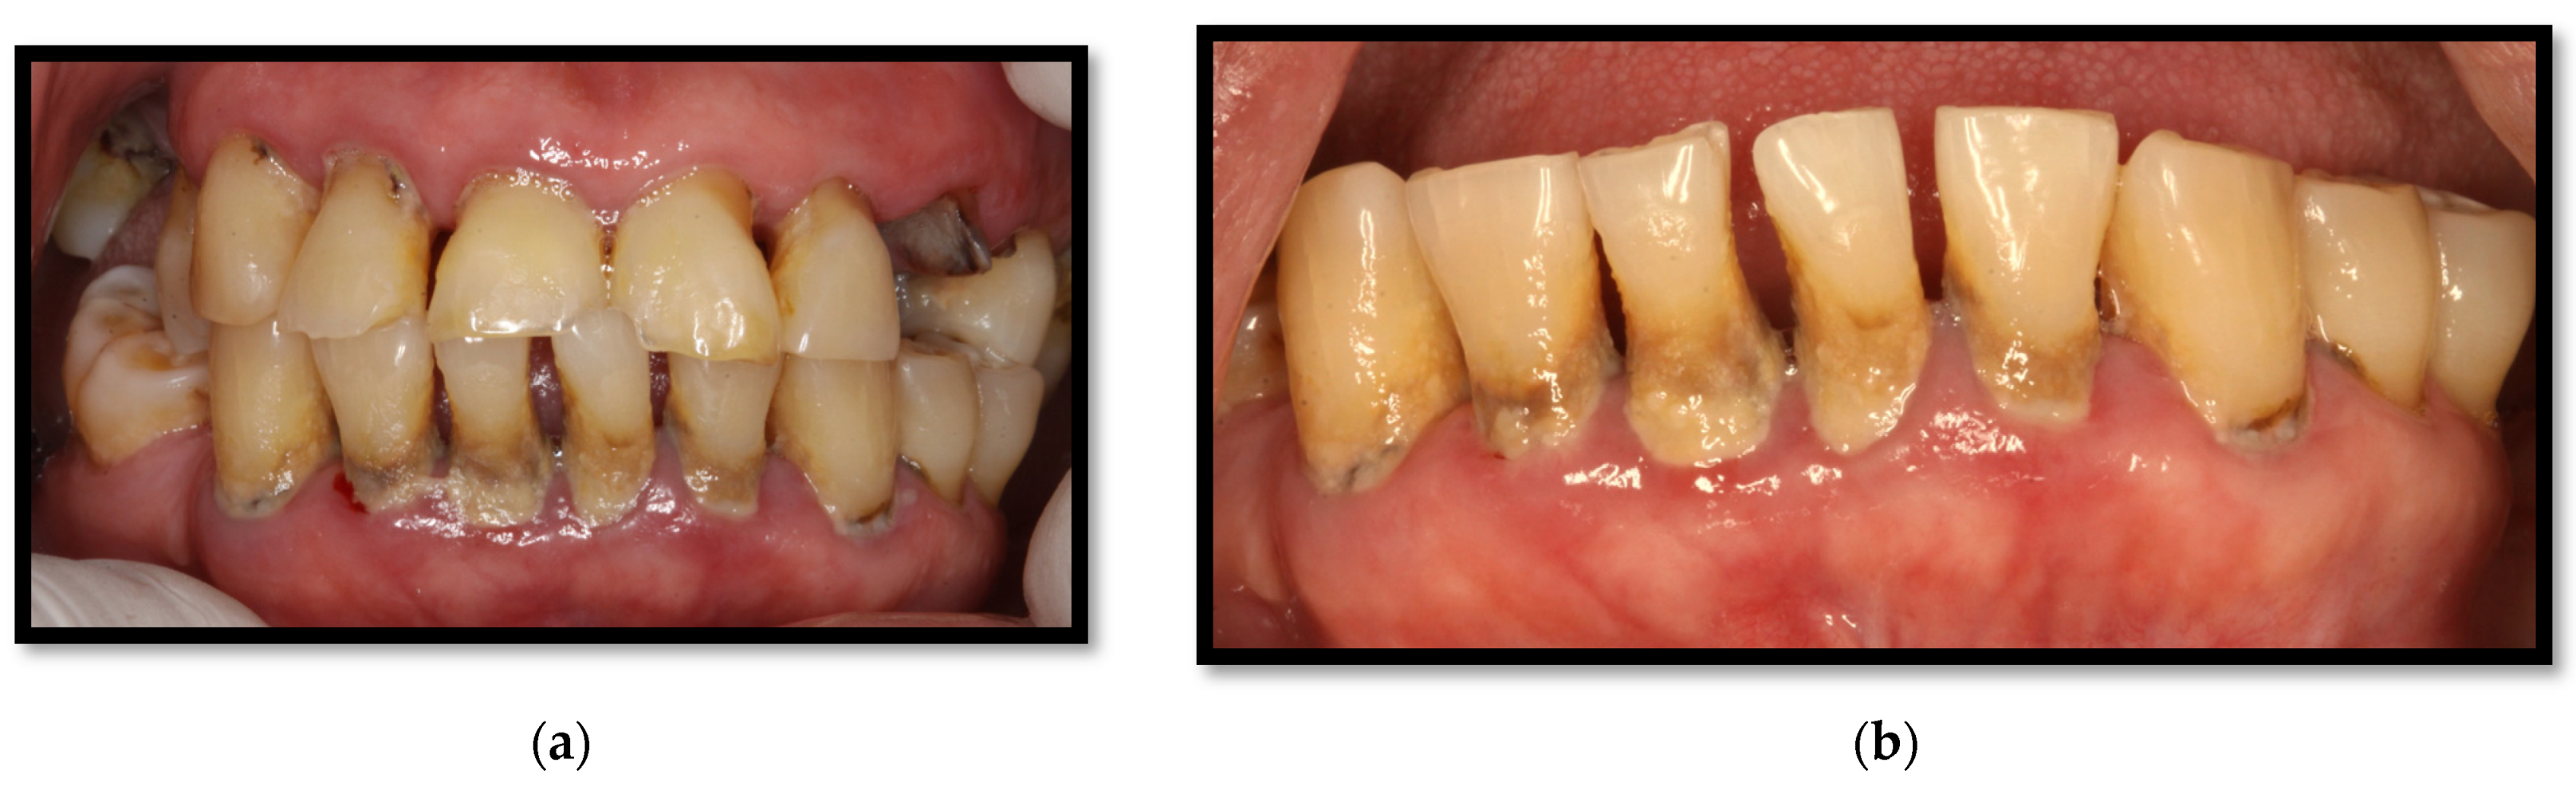

Caries can affect one or multiple dental surfaces; however, studies on the clinical characteristics and behavioral patterns of dental caries among HIV patients are scarce. Rezaei-Soufi et al. showed in their study a significant difference in the number of carious surfaces, including roots and crowns, in HIV-positive patients compared to HIV-negative patients. However, the prevalence of root caries is not significantly different between the two groups [51]. Additionally, it has been suggested that the severity of dental caries increases significantly with age and the duration of ART [51]. Within recent years, it has been suggested that C. albicans might increase caries development in patients who have HIV/AIDS, considering its capability to produce lactic acid through carbohydrate fermentation and hydroxyapatite dental structure degeneration processes, which is complicated with greater severity and the progression of caries development [10,11].

On the other hand, saliva has an essential role in preventing dental caries development due to its antibacterial and antifungal properties. It also possesses pH-buffering features within the oral cavity through bicarbonate and phosphate. As well, it provides necessary calcium and phosphate substrates to maintain dental enamel integrity. Lastly, saliva is also capable of producing antibodies [34]. HIV infiltration, CD8+ T lymphocyte proliferation within salivary glands, as well as antiretrovirals decrease the quality and quantity of salivary flow and modifies the normal oral cavity microbiome [8]; for this reason, these are considered the main risk factors for dental caries development in HIV-positive patients. Adding to the already mentioned predisposing conditions, suboptimal oral hygiene, tobacco use, drugs, periodontal disease, and a carbohydrate-rich diet are relevant factors leading to substantial dental caries development in this population (Figure 15a,b) [34,50].

Figure 15.

Multiple dental caries. (a) Front view, softened tissue in cervical and interproximal areas; (b) Lateral View, softened tissue in cervical areas.